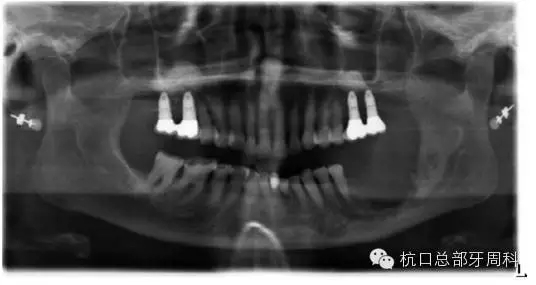

被診斷為種周炎時(shí)全景片  2011

111.webp.jpg